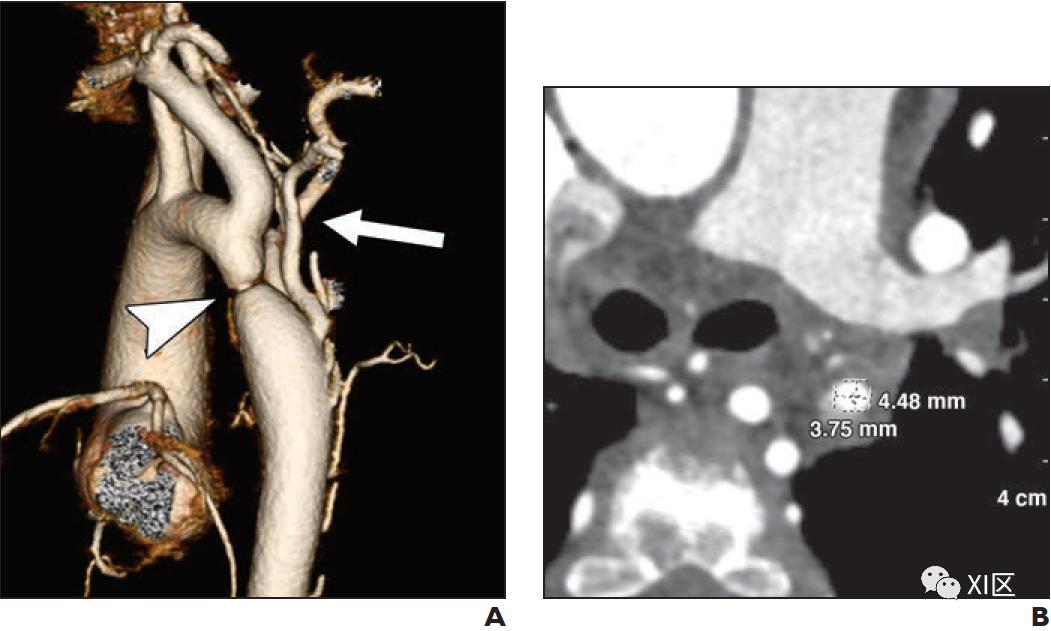

AC在子宫内很难诊断。如果未在产前发现,AC患者通常在婴儿期出现动脉导管闭合后股动脉搏动延迟或减少、臂-腿血压梯度或杂音。经胸超声心动图是AC的主要产后成像方式,但可能受到声窗的限制。CTA可提供高空间分辨率的主动脉完整显示。第三代双源CT扫描仪上提供的大螺距采集可减少心脏和呼吸运动伪影,并且通常无需心电门控,前提是不怀疑心内或冠状动脉异常。此外,斜位多平面和三维重建提供了直观的术前计划。CTA和超声心动图在术前定量测量中被证明是等效的。典型的CTA表现包括主动脉弓局灶性偏心狭窄,多条扩张的侧支动脉绕过狭窄段(图6)。当狭窄纵向跨度超过5毫米时,可诊断为管状发育不全。术前评估应包括测量近端横弓(无名动脉和左颈总动脉之间)、远端横弓(左颈总动脉和左锁骨下动脉之间)、峡部的主动脉直径,以及缩窄的部位(图6)。其他相关的发现包括弓分支模式和弓血管之间的距离。

儿童主动脉病

主动脉瘤和主动脉夹层在小儿中很少见。然而,一些结缔组织疾病使儿科患者容易形成动脉瘤和动脉夹层,其中最显著的是马凡、Ehlers-Danlos和Loeys-Dietz综合征等(图10和表3)。此外,除了可识别的遗传综合征外,主动脉瘤还具有遗传倾向,主动脉瘤患者的一级亲属自身发生动脉瘤的风险增加10-12倍。对潜在动脉瘤易感综合征患者的评估通常需要对整个胸部、腹部和骨盆进行成像,尽管已知有些疾病只影响部分主动脉。当评估主动脉根部扩张时,ECG门控确保没有心脏运动伪影。多平面重建和双斜面测量对于弯曲的血管的精确和可重复测量必不可少。考虑到儿童身体尺寸的正常变化,主动脉大小异常没有绝对阈值。相反,主动脉大小与根据体表面积计算的人群z评分进行比较。